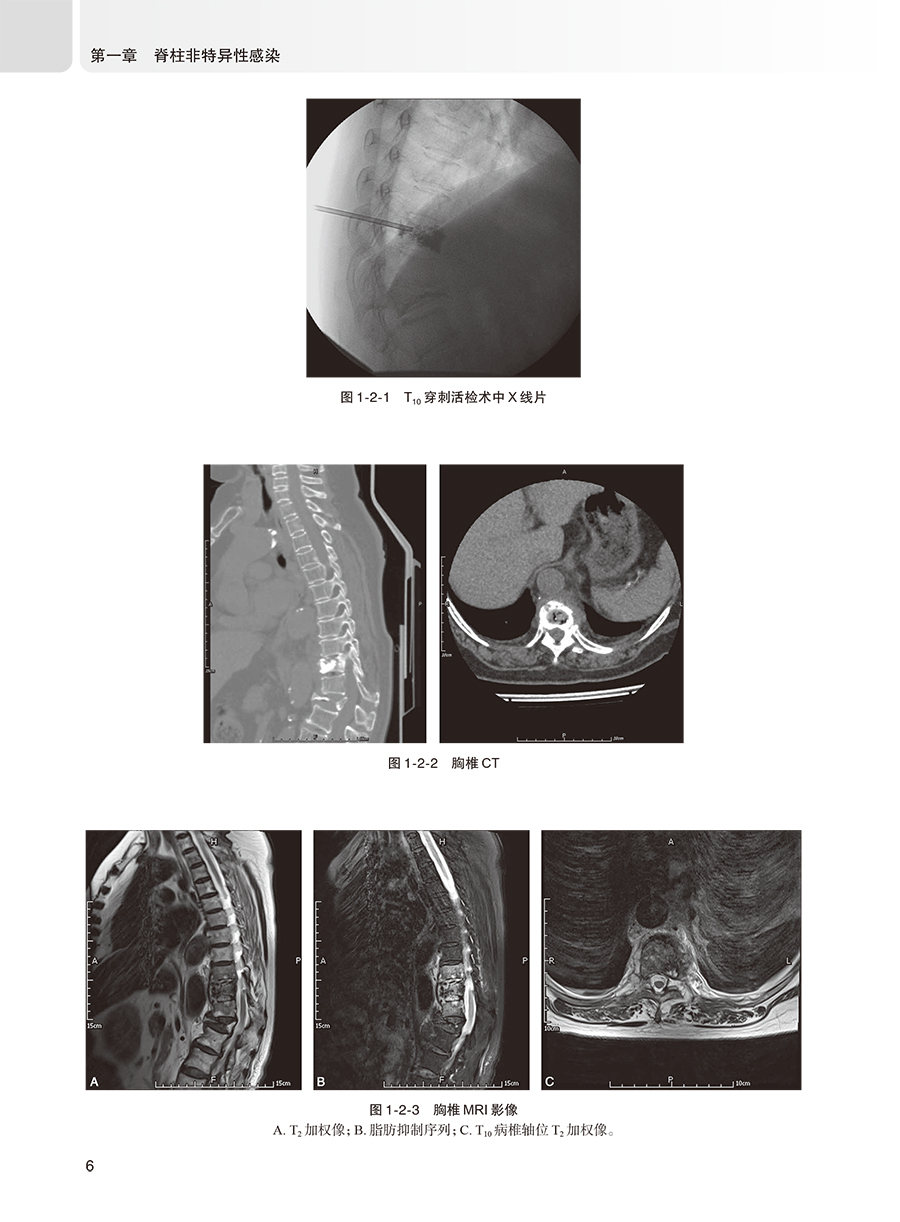

脊柱感染性疾病是指由不同病原微生物引起的脊柱不同部位(椎体、椎间盘、附件、椎管和邻近椎旁组织)的一系列感染性疾病,约占全身骨骼肌肉系统感染的2%~7%。脊柱感染性经典分类法可分为特异性感染和非特异性感染两种类型。脊柱特异性感染包括结核分枝杆菌感染、非结核分枝杆菌感染、布鲁氏杆菌感染、真菌感染和寄生虫感染。脊柱非特异性感染包括金黄色葡萄球菌感染、表皮葡萄球菌感染、大肠埃希菌感染、链球菌感染、肺炎克雷伯菌感染、铜绿假单胞菌感染、粪肠球菌感染、屎肠球菌感染、沙门氏菌感染等。本书将针对不同类型的脊柱感染,先进行概述,之后从临床表现、影像学检查、病理学和实验室检查、非手术治疗、手术适应证和禁忌证、术前准备、手术步骤、术后处理等方面进行阐述,最后附上2~3个经典病例。这些经典病例是本书的精髓所在,旨在加深读者对该疾病的理解和认识。每个病例的展示包括病史、症状、体征、影像学和实验室检查、诊断思路、术前处理、手术方法、术后管理措施,以及对该疾病的研究现状和**进展等,力争将该疾病的诊断和治疗方法阐述更加得鲜活生动。每个病例争取都具有一定代表性,在诊断和治疗上具有一定难度,达到读者有受益匪浅的感觉。随着脊柱结核手术在基层医院的逐步开展,手术失败需要翻修的患者逐年增多,此类患者手术难度大,并发症发生率高,基层医院难以完成。针对这一问题,本书将对脊柱结核手术失败翻修病例进行展示,详细阐述脊柱结核手术失败的诊断、治疗原则、手术入路选择、手术技术要点及预后。脊柱结核患者误诊行椎体强化术的问题日趋严重,脊柱外科医生对这个问题的认识存在误区,其结果是对患者产生灾难性后果。针对这一临床常见问题,本书将详细阐述脊柱结核误诊行椎体强化术患者的治疗原则和方法,及远期效果,加深同行对该问题的认识。